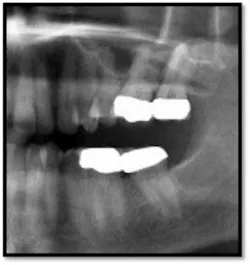

TX FM Perioscopy with local anesthetic FM LANAP Surgical Procedure •bone sounding was performed on all teeth included in this procedure •occlusal adjustment performed resulting in reduction in centric prematurities •Orthodontic referral for anterior spacing •3 month periodontal maintenance14 months post TreatmentPocket reductions of up to 4mm

Conclusion:

The patient now has a stable dentition and has moved forward with Invisalign orthodontia to correct the overbite and spacing in her anterior teeth.

The posterior crowns still present a challenge to keep clean and will be scheduled for replacement post orthodontic treatment.

She is enrolled in periodontal supportive therapy every 3 months.